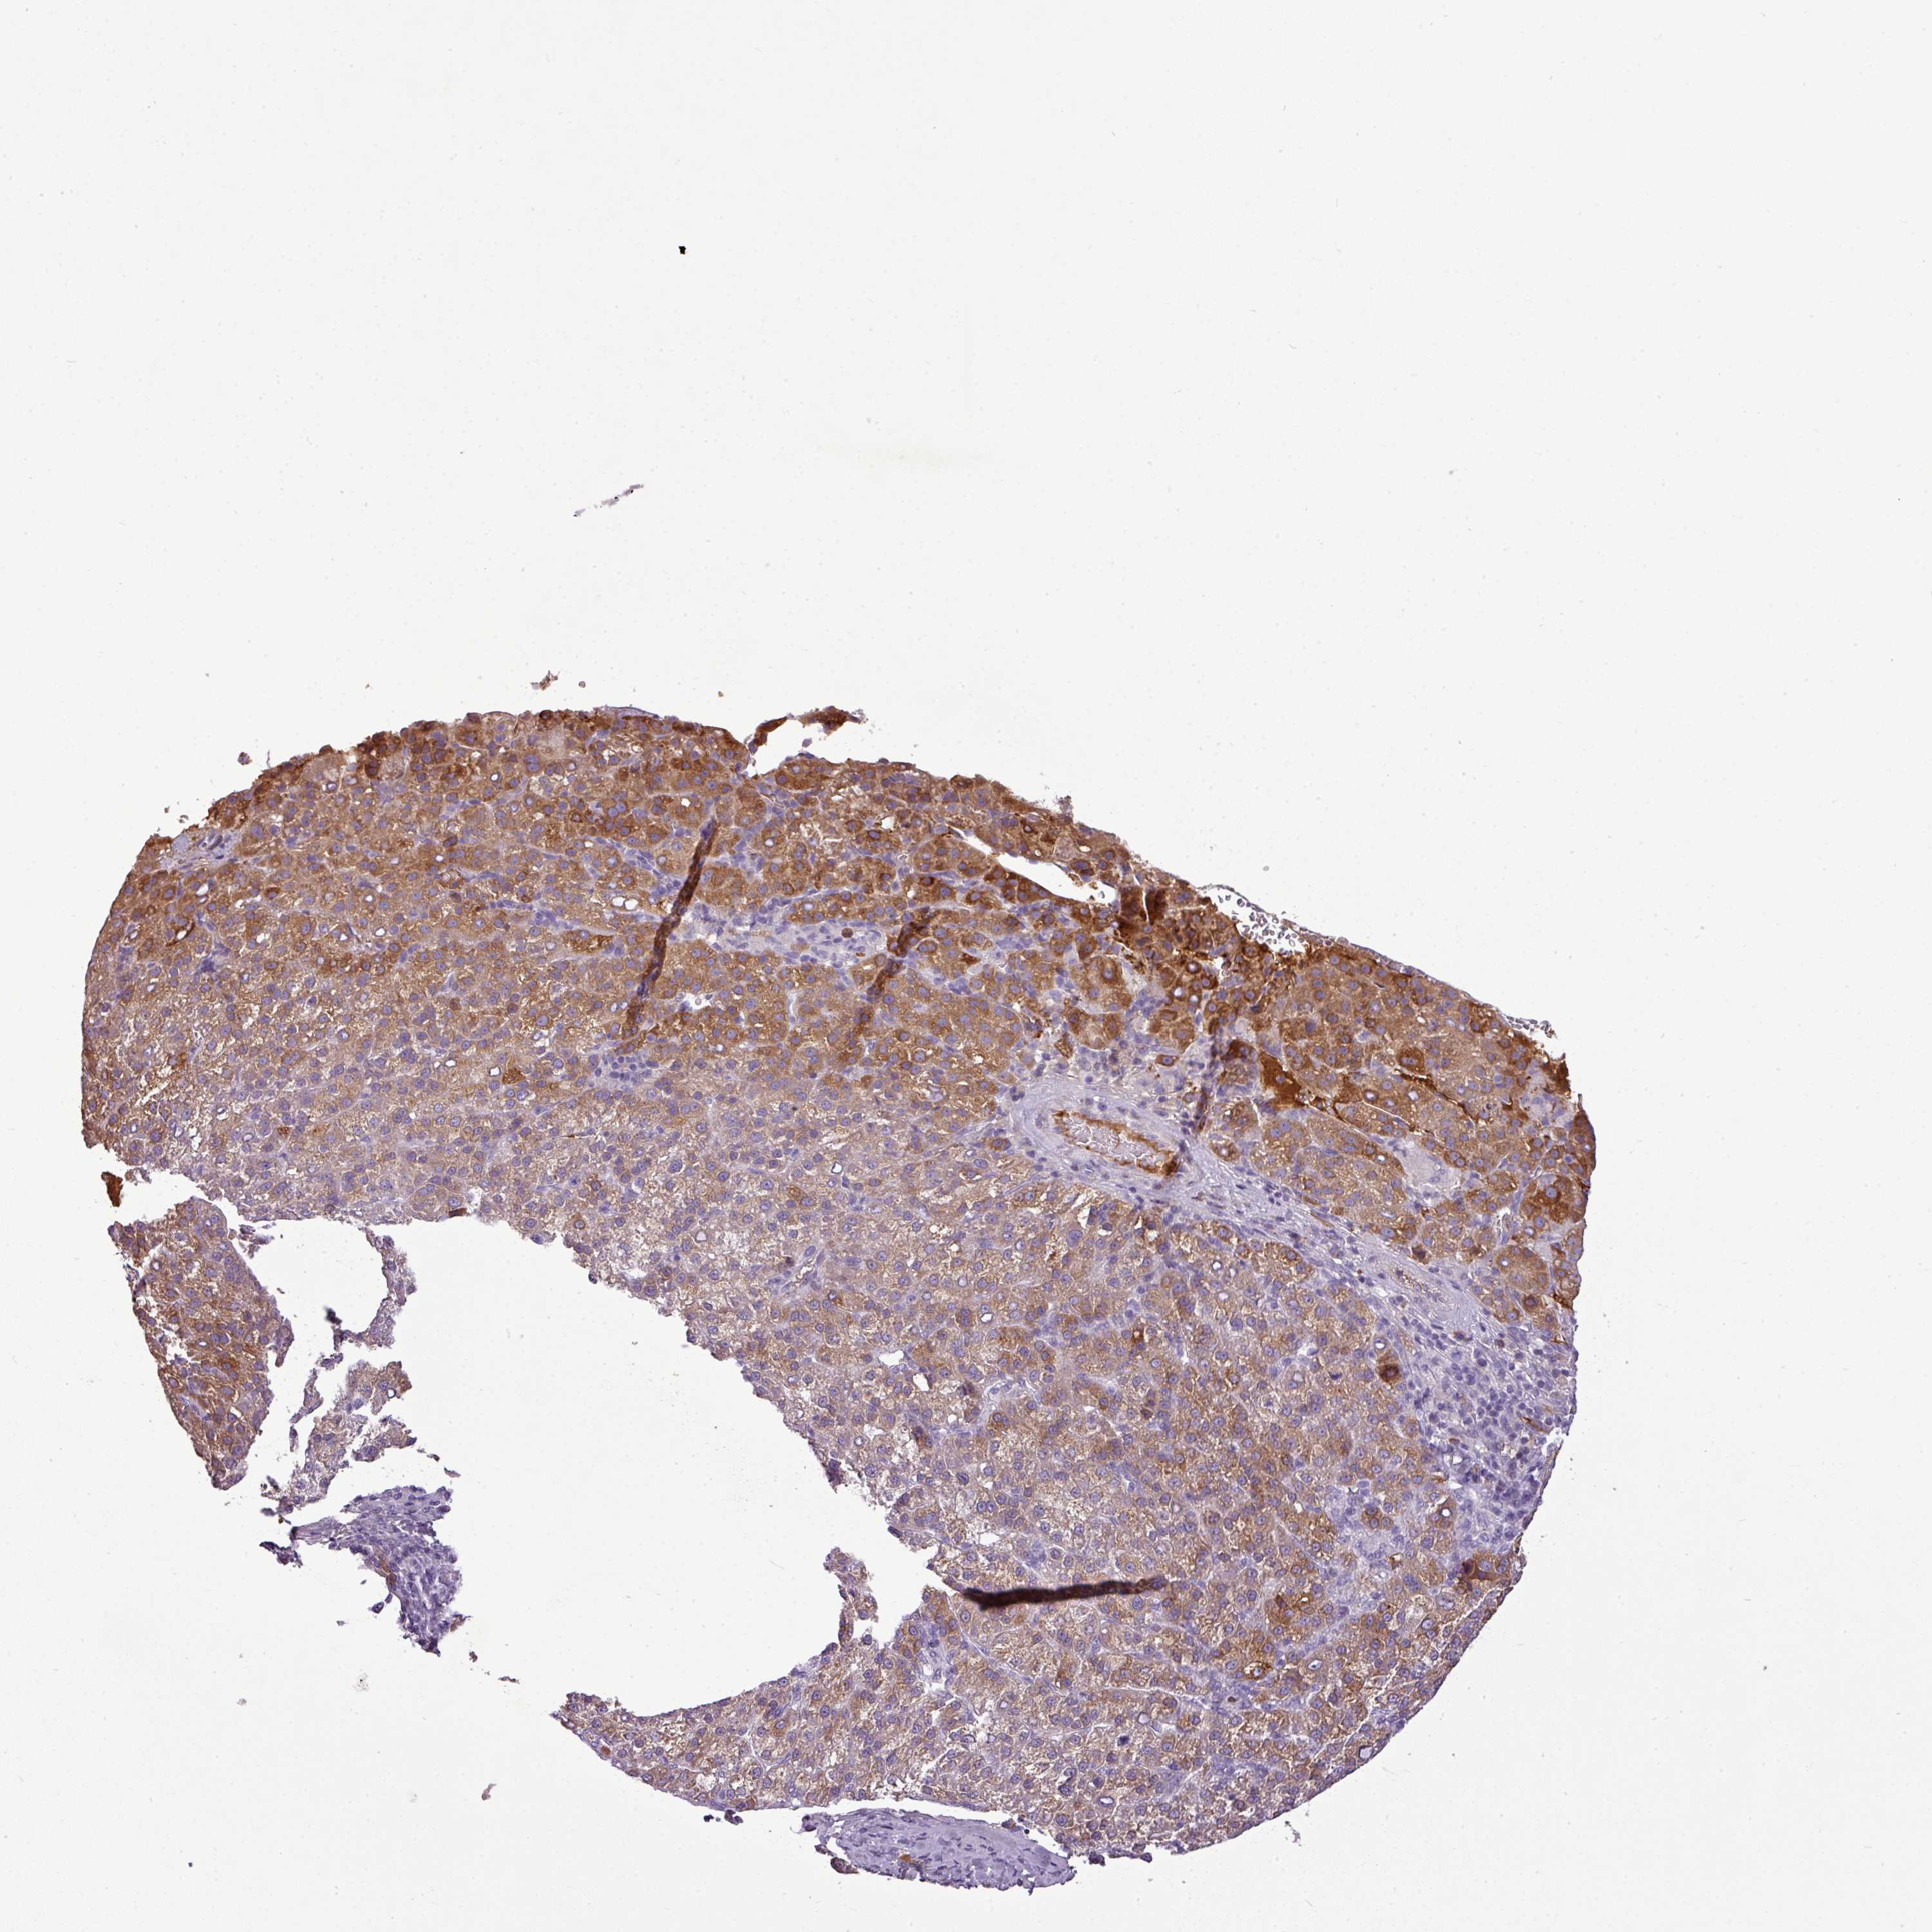

LIVER CANCER - Protein expressioni

A mouse-over function shows sample information and annotation data. Click on an image to view it in a full screen mode. Samples can be filtered based on level of antibody staining by selecting one or several of the following categories: high, medium, low and not detected. The assay and annotation is described here.

Note that samples used for immunohistochemistry by the Human Protein Atlas do not correspond to samples in the TCGA dataset.

Antibody stainingi

Antibody staining in the annotated cell types in the current human tissue is reported as not detected, low, medium, or high, based on conventional immunohistochemistry profiling in selected tissues. This score is based on the combination of the staining intensity and fraction of stained cells.

Each image is clickable and will lead to virtual microscopy that enables deeper exploration of all samples and also displays staining intensity scores, fraction scores and subcellular localization as well as patient and tissue information for each sample.

HPA046356

HPA048287

HPA050103

CAB009811

CAB032603

Staining

High

Medium

Low

Not detected

Intensity

Strong

Moderate

Weak

Negative

Quantity

>75%

75%-25%

<25%

None

Location

Nuclear

Cytoplasmic/membranous

Cytoplasmic/membranous,nuclear

Cholangiocarcinoma

Carcinoma, Hepatocellular, NOS